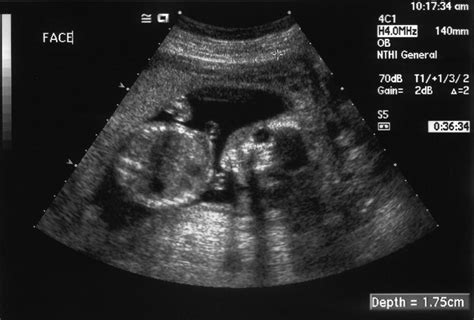

Umiestnenie placenty v maternici môže byť rôzne - na prednej, zadnej, hornej alebo bočnej stene. Každá z týchto polôh je fyziologická, ale môže mať odlišný vplyv na niektoré aspekty tehotenstva. Tieto polohy sa spoľahlivo identifikujú pomocou ultrazvukového vyšetrenia.

Diagnostika placenty praevia zahŕňa ultrasonografické vyšetrenie. Vaginálne krvácanie po druhom trimestri by malo upozorniť gynekológa na možnosť placenty praevia. Digitálne vyšetrenie je v tomto prípade kontraindikované. Transvaginálna ultrasonografia je bezpečná a odporúčaná metóda na potvrdenie alebo vylúčenie diagnózy.